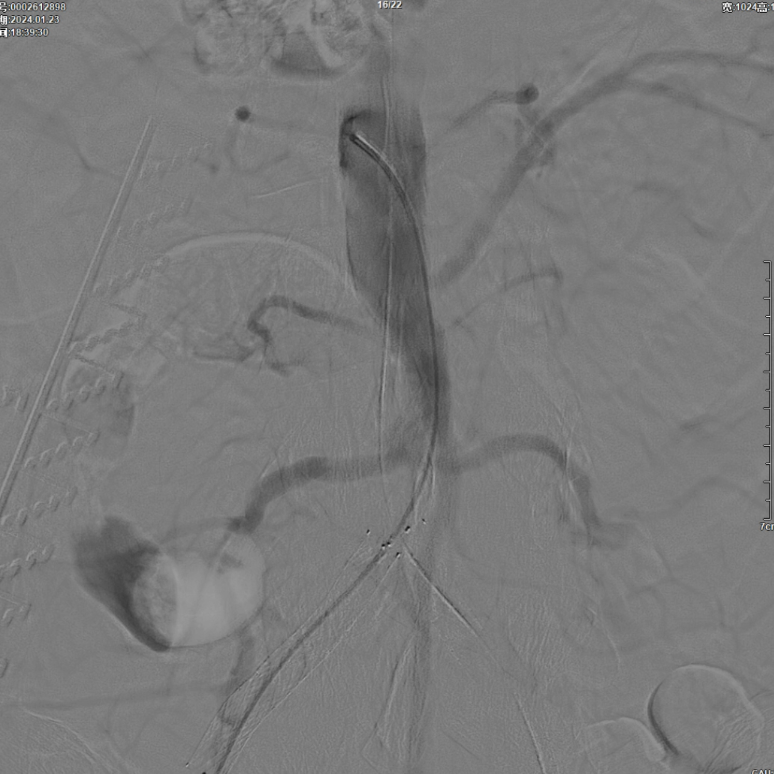

右侧髂外动脉存在残存狭窄,因该部位无原有裸支架覆盖,为节省治疗费用,选择植入1枚直径8mm的裸支架,并采用8mm球囊进行后扩张。

即时效果:造影显示腹主动脉、双侧髂总/髂外动脉及股动脉通畅。

3个月复查:右侧股动脉完全再通,无残存狭窄;CTA显示腹主动脉、双侧髂动脉及远端股动脉通畅,双侧ABI>1.0;左侧髂动脉开口打开不全(推测与对吻球囊直径选择有关,原用8mm,若选10mm可能避免),因患者无症状,暂密切随访,远期若再狭窄可采用10mm球囊扩张。